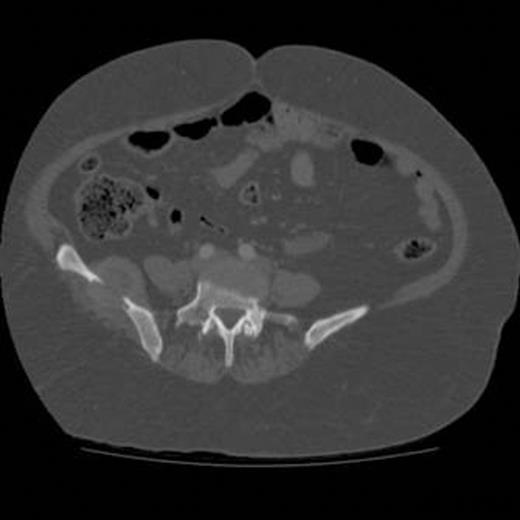

A 59-year old Afghani woman presented initially to the acute medical team with a history of hypokalaemia and hypertension. Investigations confirmed non-suppressed hyperaldosteronism and computerised tomography (CT) imaging of the abdomen confirmed adenoma of the left adrenal gland. However, imaging also noted an incidental finding of a soft tissue mass in the right iliac bone measuring 4.5cm transversely (Fig. 1). Initial differentials included plasmacytoma and chondroma.

Axial CT image of abdomen demonstrating the mass noted in the right iliac bone of the pelvis measuring 4.5cm transversely.